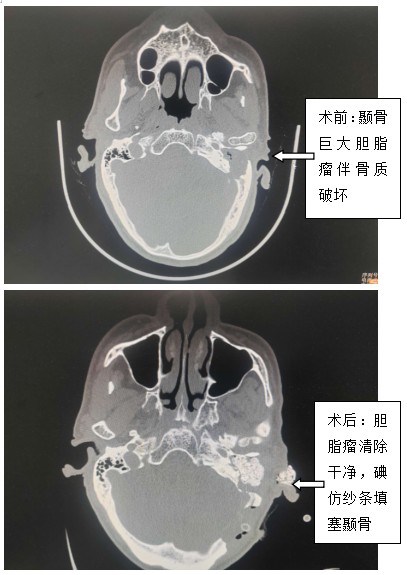

近年來,姚大爺被檢查出來有糖尿病,所以每次去醫(yī)院總是為了控制血糖。一星期前,姚大爺再次出現(xiàn)耳部流膿及血糖控制不佳,往醫(yī)院抽血檢查竟然發(fā)現(xiàn)血糖20.3mmol/l。醫(yī)生建議住院治療,可是姚大爺在住院后經(jīng)過控制血糖后,發(fā)現(xiàn)耳朵雖然不流膿了,但是頭痛的越來越厲害,而且出現(xiàn)走路不穩(wěn)癥狀,一查CT,竟然發(fā)現(xiàn)小腦出現(xiàn)了一個(gè)30*20mm的膿腫,同時(shí)左側(cè)中耳及顳骨有一個(gè)巨大腫瘤(膽脂瘤),于是當(dāng)?shù)蒯t(yī)院通過醫(yī)聯(lián)體??坡?lián)盟專家會(huì)診,建議轉(zhuǎn)院急診手術(shù)。經(jīng)過長(zhǎng)達(dá)5小時(shí)的手術(shù),術(shù)中耳鼻喉科茹江云、庾江東、漆德良團(tuán)隊(duì)顯微鏡下清除中耳及顳骨巨大膽脂瘤,同時(shí)神經(jīng)外科李遠(yuǎn)志、李芳團(tuán)隊(duì)予以行乙狀竇后入路小腦膿腫清除手術(shù),病人暫時(shí)脫離生命危險(xiǎn)。